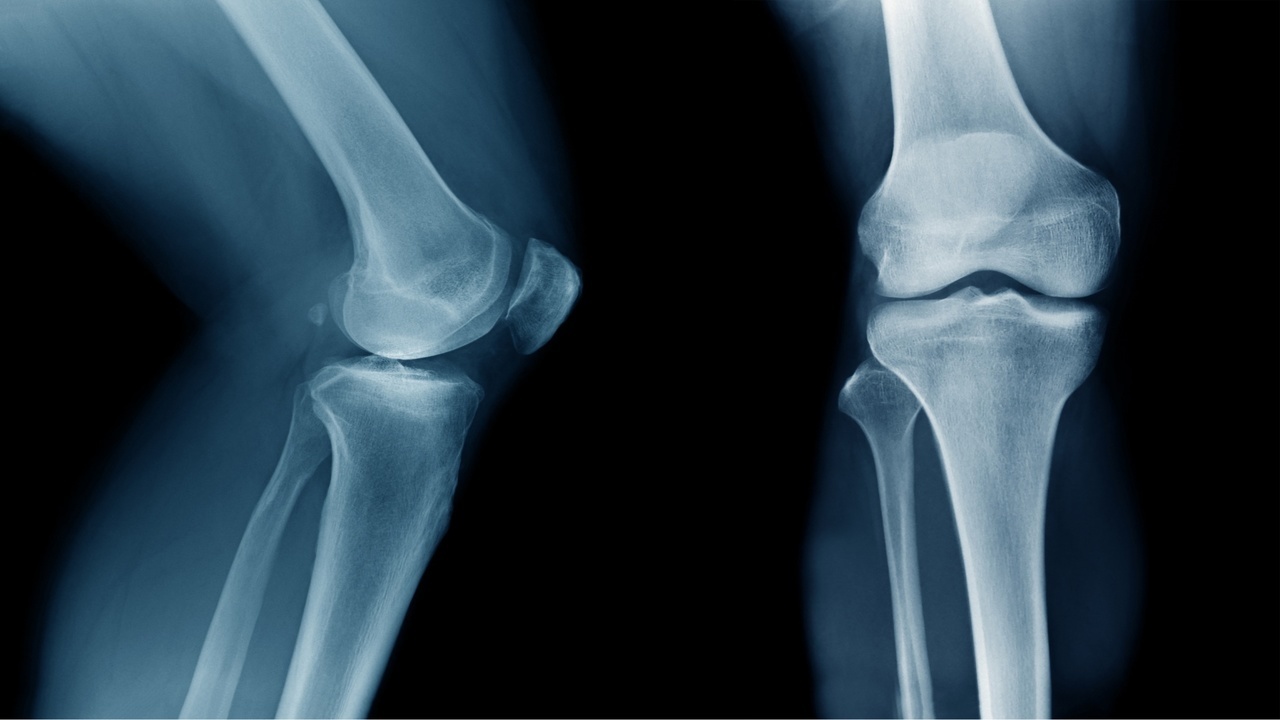

変形性ひざ関節症とは??

変形性膝関節症は、膝の関節にある軟骨や半月板の摩耗により痛みや炎症を引き起こす疾患です。

摩耗はじわじわとゆっくり進行するため、はじめは膝に小さな違和感がある程度でも徐々に状態が悪くなっていきます。

初期の変形性膝関節症を無視してしまうと、軟骨のかけらによる刺激で炎症が起こり膝に水が溜まり腫れてくる事があります。

膝関節液が過剰に分泌され、熱を持ち徐々に状態が悪くなり最終的には膝を守っている軟骨や半月板が破損。

大腿骨と脛骨が直接ぶつかるようになり、日常的に膝の痛みを発症していきます。